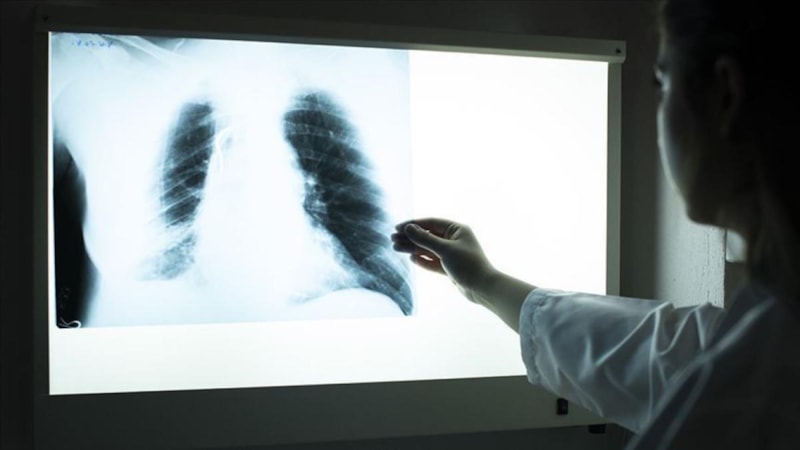

Akciğerde kalsiyum birikirse (kalsiyum oksit, kalsiyum karbonat, kalsiyum sülfat gibi kimyasallara uzun süreli maruz kalınan mesleklerde) akciğer filminde beyaz lekelenmeler görülür.